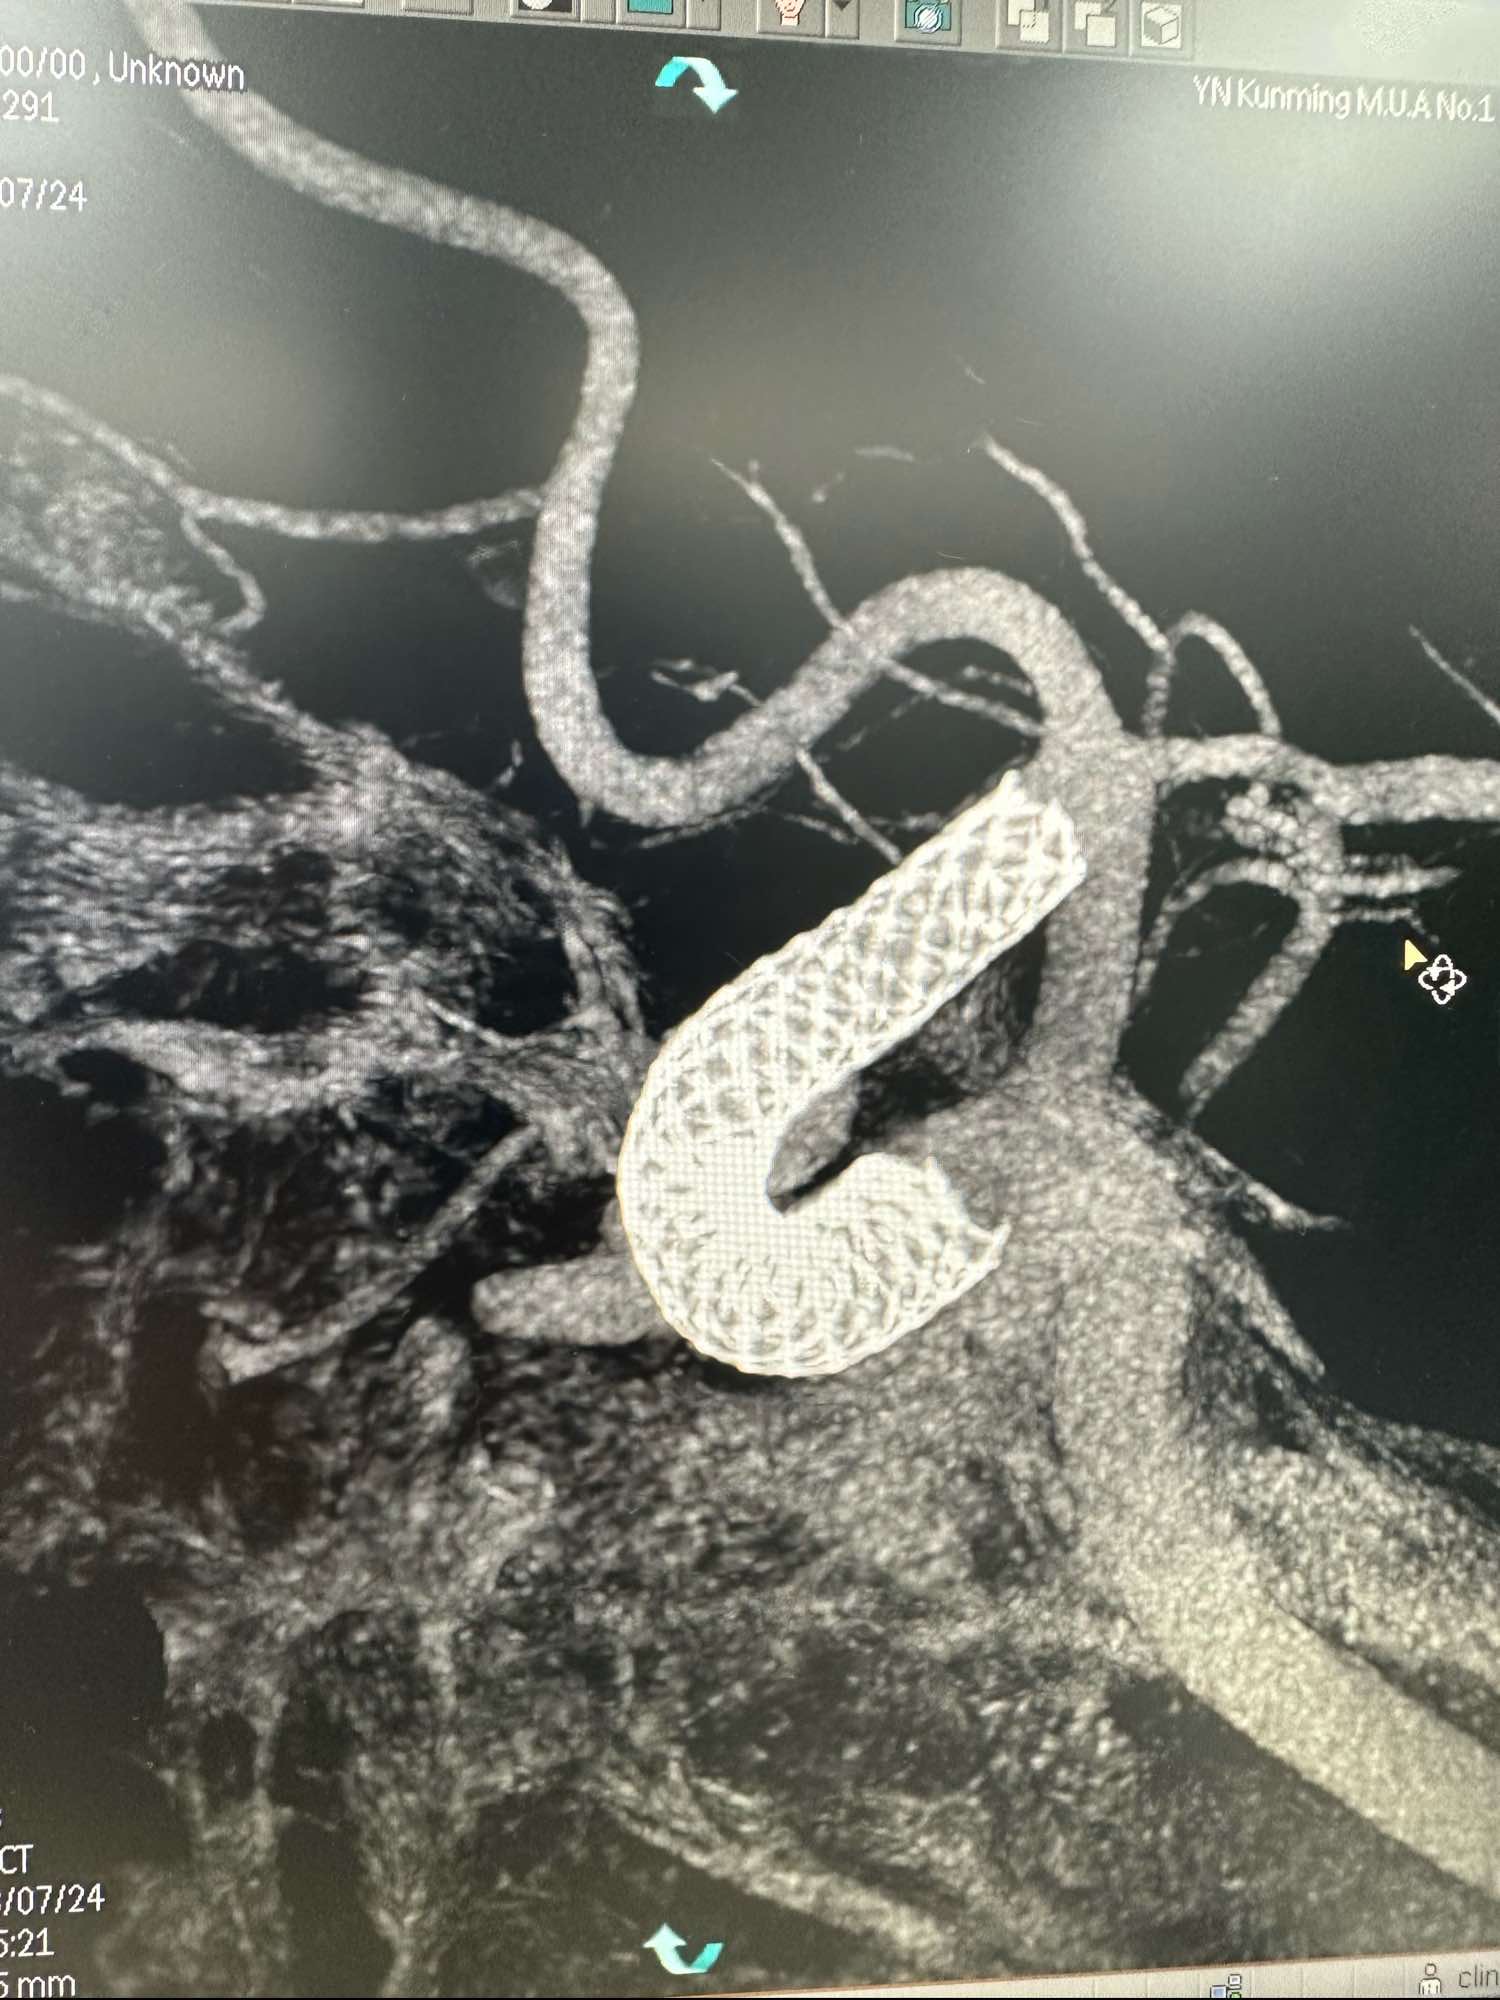

术前的3D